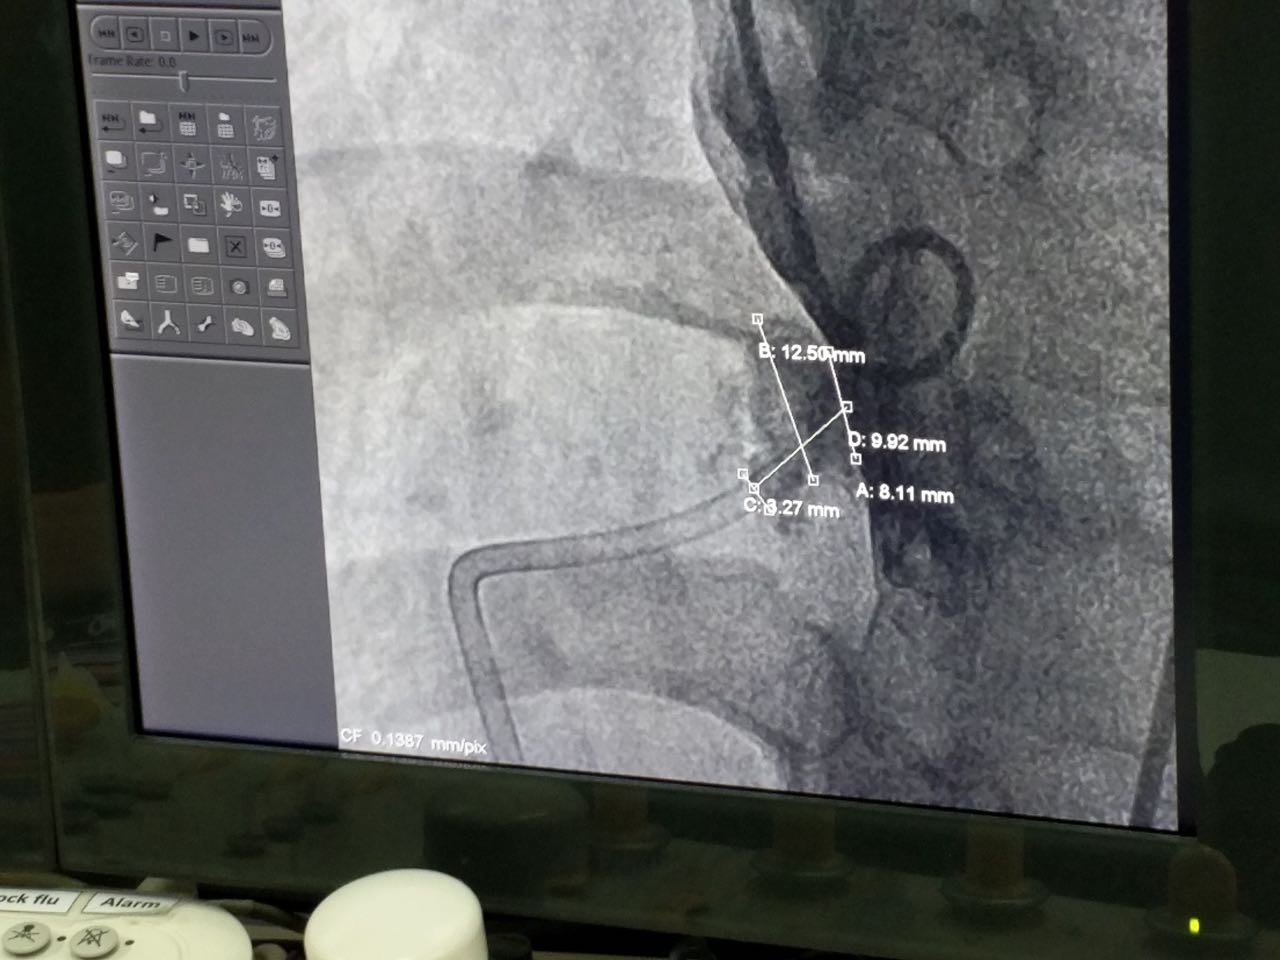

第四例手术患者经诊断为膜周部室间隔缺损并伴有室缺瘤。术中测量患者瘤体直径为12.5mm,左室入口为9.92mm,右室出口为3.27mm,且其室间隔缺损位置较为特殊,位于主动脉瓣正后方并非常靠近三尖瓣。病人同时具有三尖瓣反流的症状。本例手术的主要术者Dr.Pimpak Prachasilchai选用彩神在线网信彩票-彩神通免费版下载-彩神8争霸vlll-彩神购彩购彩大厅-彩神软件陆立根免费版-彩神ll争霸3-彩神ll彩神8-彩神ll争霸彩票-拼搏在线彩神网网页版科技公司型号为LT-MFO-8-6的KONAR-MF™多功能封堵器,通过主动脉路径释放成功。病人缺损部位封堵完全,无残余分流,三尖瓣未受干扰。

(术中造影)